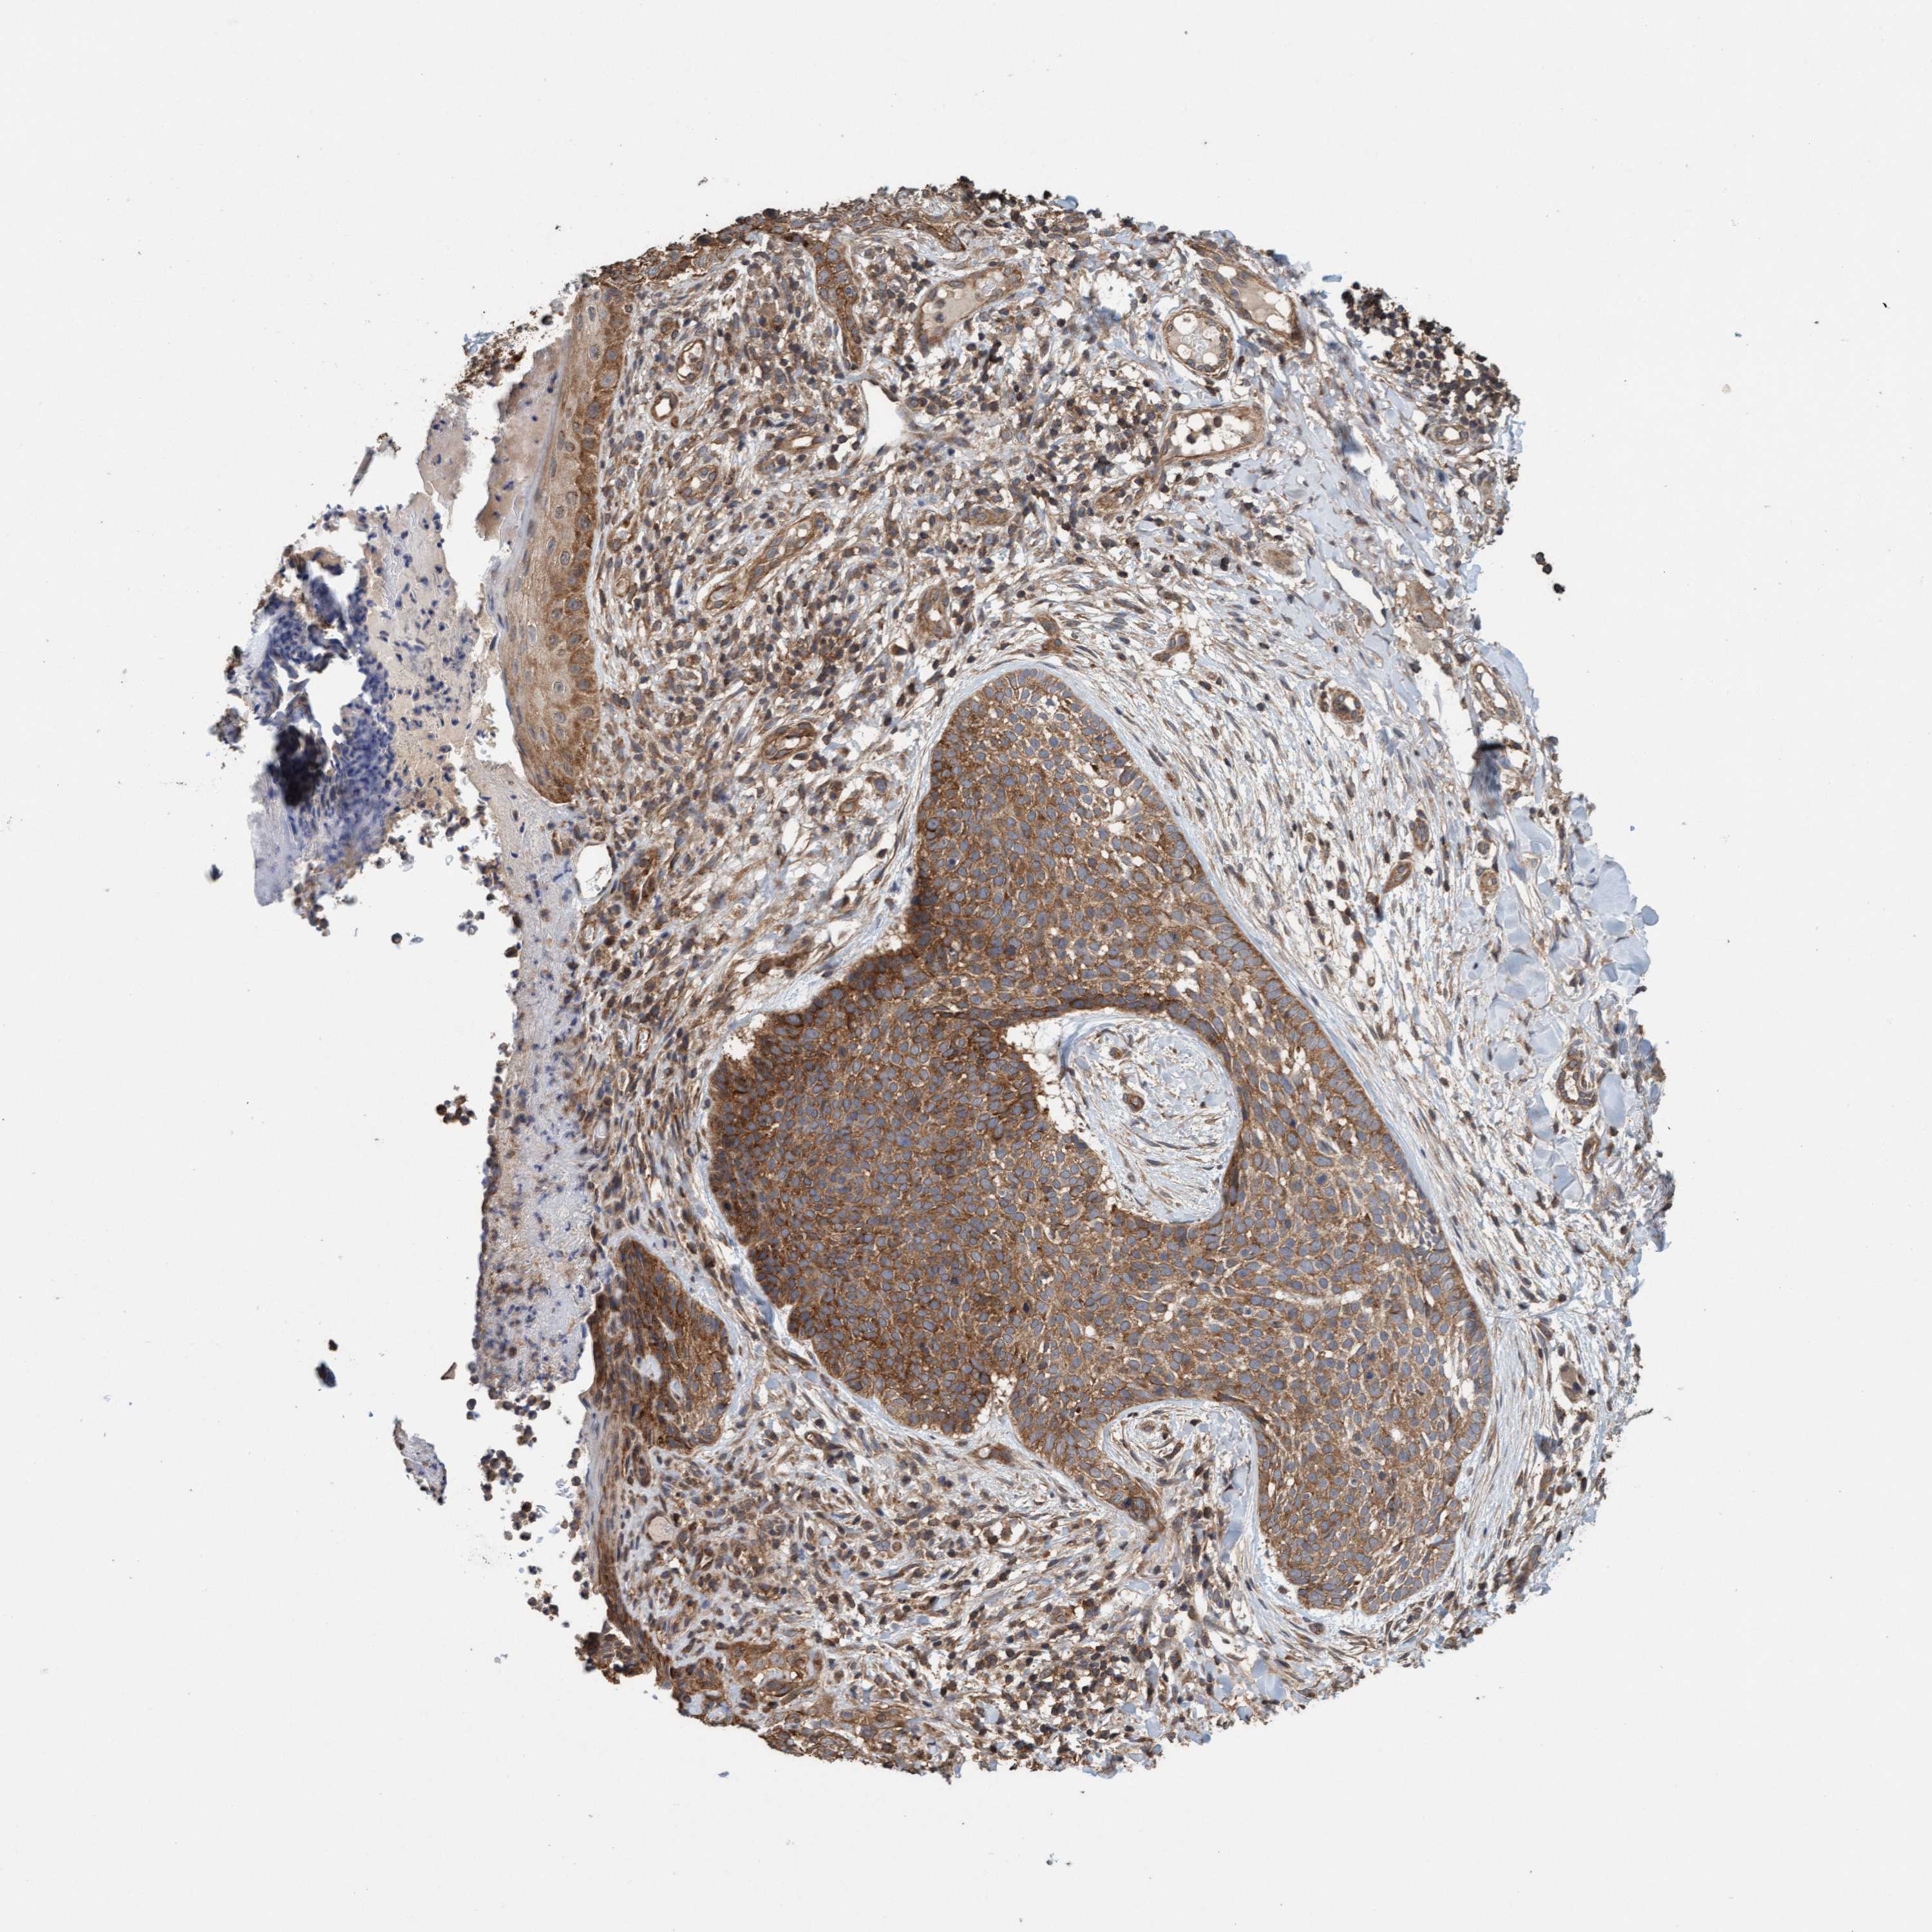

CANCER SKIN CANCER Show tissue menu

Basal cell and squamous cell cancer

SKIN CANCER - Protein expressioni

A mouse-over function shows sample information and annotation data. Click on an image to view it in a full screen mode. Samples can be filtered based on level of antibody staining by selecting one or several of the following categories: high, medium, low and not detected. The assay and annotation is described here.

Each image is clickable and will lead to virtual microscopy that enables deeper exploration of all samples and also displays staining intensity scores, fraction scores and subcellular localization as well as patient and tissue information for each sample.

Antibody HPA022997

Basal cell carcinoma

Squamous cell carcinoma, NOS

Squamous cell carcinoma, metastatic, NOS

Adnexal tumor, benign